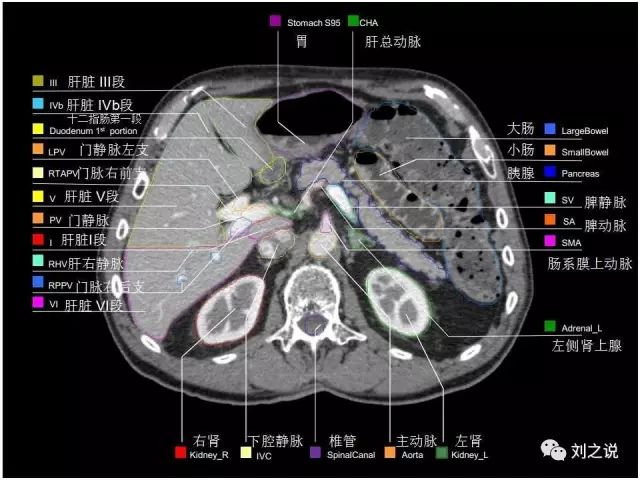

参考RTOG共识和3D-body解剖。

来源:刘之说